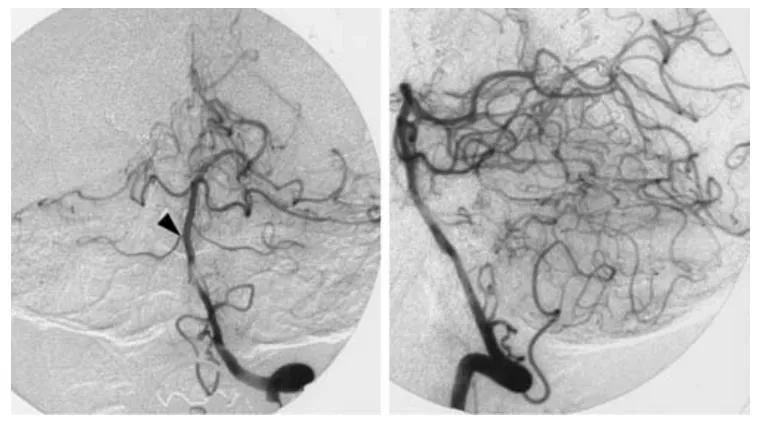

手术后,患者出现了右侧三叉神经第一支与第二支分布区的部分感觉减退症状。复查血管造影证实动静脉畸形已被完全切除,影像上仅可见单支小脑上动脉(图4)。

图4 左侧椎动脉数字减影血管造影正位(左图)与侧位(右图)像,显示无残余动静脉畸形,仅可见1支右侧小脑上动脉(箭头端指示)